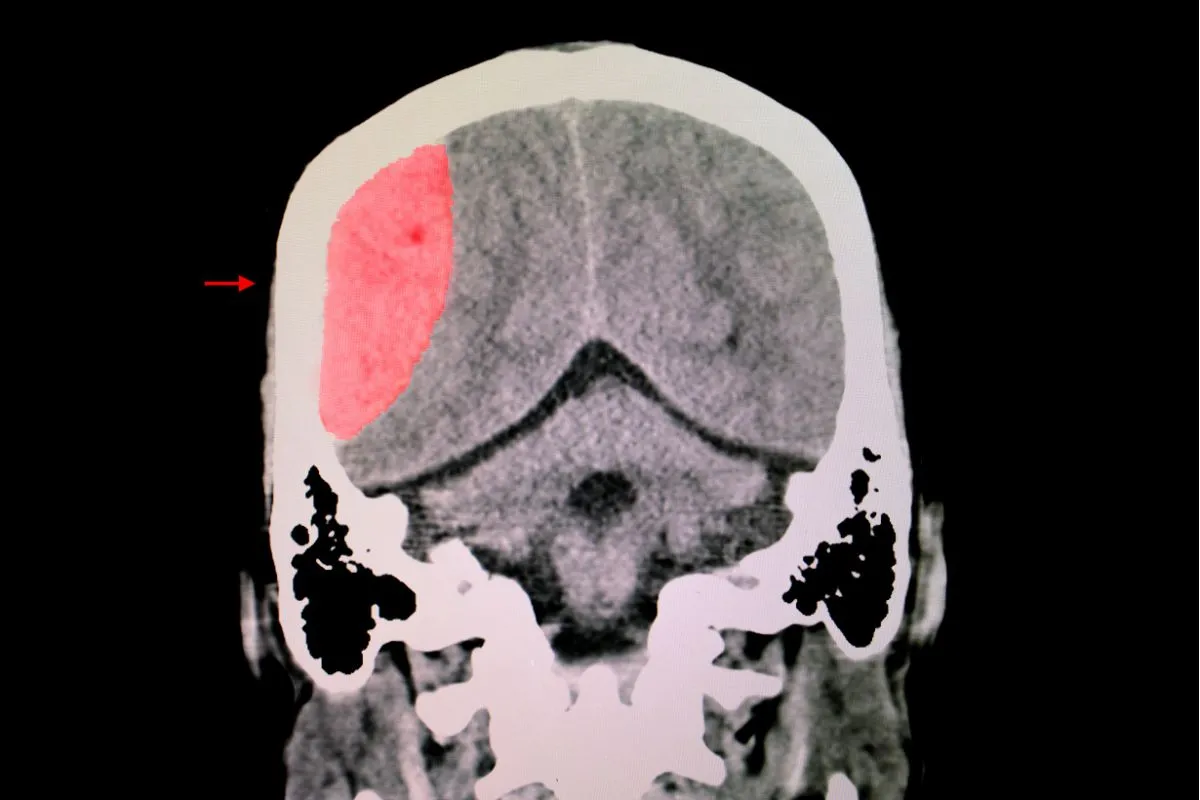

TBI affects over 1.4 million Americans annually. The leading cause of TBI is falls, followed by motor vehicle crashes. Moreover, blasts are a leading cause for active-duty military personnel. Called the “signature injury” of the Iraq War, some accounts estimate that up to 60% of injuries related to roadside bombs in Iraq are TBIs. Symptoms include memory loss and communication problems; even worse, perhaps, are the behavioral and psychological ramifications. Formerly balanced, responsible, and mature adults may become impulsive, irrational, and depressed.